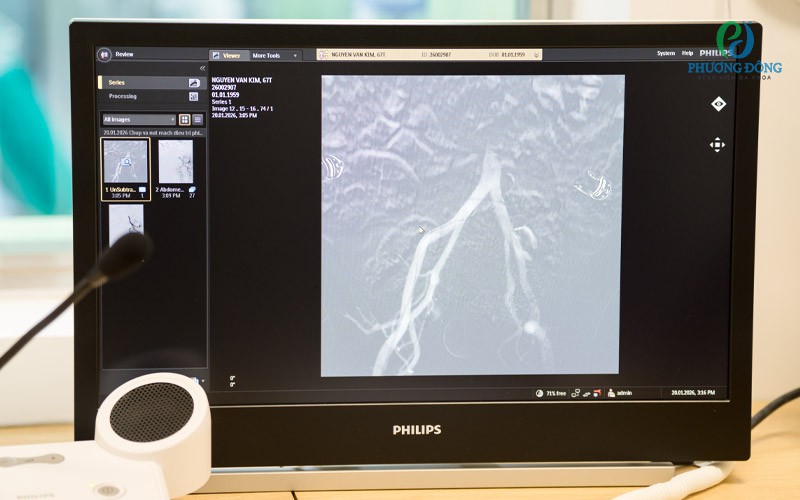

Hình ảnh mạch máu sau chụp được hiển thị vô cùng chi tiếtHình ảnh mạch máu sau chụp được hiển thị vô cùng chi tiết